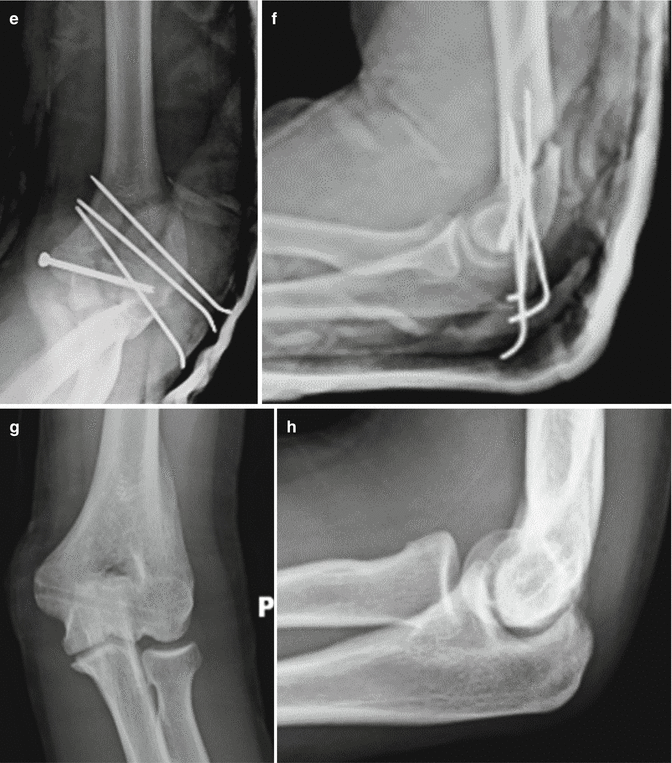

S40S49 Injuries to the shoulder and upper arm ;. INTRODUCTION Tcondylar fractures of the humerus are very rare in children The treatment options vary from simple reduction and percutaneous stabilisation to open reduction and fixation with plates, screws and Kirchner wires We evaluated 19 patients who underwent different types of treatment aiming to compare two different approaches of. Tcondylar (intercondylar) fracture of the humerus is a very rare occurrence in the paediatric age group Incidence of this type of fracture is unknown since the majority of literature is limited to case reports or case series, without outlining the number of cases appearing over the time period in which the cases were observed , A paediatric intercondylar fracture can sometimes be confused with an extension type supracondylar fracture of the humerus.

Introduction Intercondylar (TCondylar) fractures of the humerus are very rare in children The usual mechanism of the injury which is involved is a fall on a flexed elbow. Tcondylar fractures of the humerus are rare injuries in children and adolescents A review of 300 consecutive cases of fractures of the elbow in children showed that this injury pattern occurs in only 2 % of cases 1. Tcondylar fractures may result from flexion or extension injury, with the articular surface of the olecranon acting as a wedge to split the humeral condyles Flexion injury is often from a fall on.

Tcondylar fracture is a type of distal humerus fracture Tcondylar fracture in children is rare, with reported incidence of less than 1% of Tcondylar fractures The mean reported age of. Although fractures of the elbow are extremely common in pediatric patients, the Ttype distal humerus fracture is rare and offers unique challenges The mechanism of injury may be similar to the adult counterpart and is usually caused by a fall onto a flexed elbow or from a direct blow Diagnosing these injuries may be difficult. Tcondylar fractures of the distal humerus are very rare in children High degree of suspicion and then further imaging are needed for these types of injuries to be detected Tcondylar fractures can have a high chance of complications Parents should be warned about the likelihood of an unsatisfactory outcome.

Pediatric Tcondylar humerus fractures requiring an open approach may benefit from less invasive approaches such as the triceps split approach where the fracture pattern allows Younger children are more amenable to less invasive means of fracture reduction and fixation If an articular reduction is required, the aggregated literature suggests that the Morrey slide offers equivalent results to the olecranon osteotomy but with fewer approachrelated complications. Blakey CM, Biant LC, Birch R Ischaemia and the of elbow fracture in children analysis of 355 pink, pulseless hand complicating supracondylar fractures, with special reference to supracondylar fractures of the humerus in childhood longterm humerus fractures. With mild lateral/valgus displacement and rotation is noted in the coronal plane No radial or ulnar fracture is notedSoft tissue swelling is noted around the elbow.